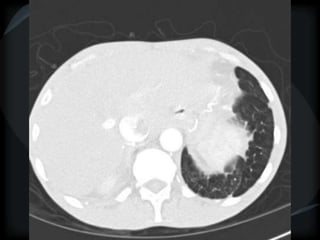

PHTN – PA 39mm

39.2mm

PHTN and septal thickening

? PVOD